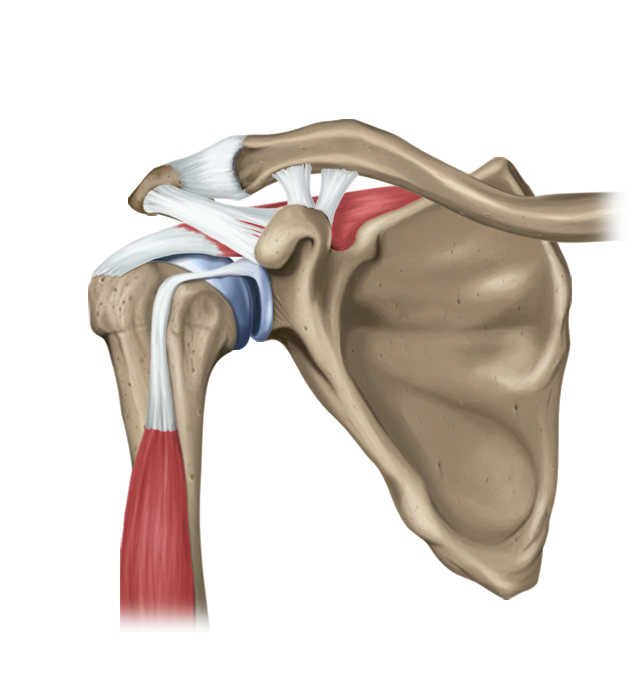

Фотографии мышц ротаторной манжеты плеча